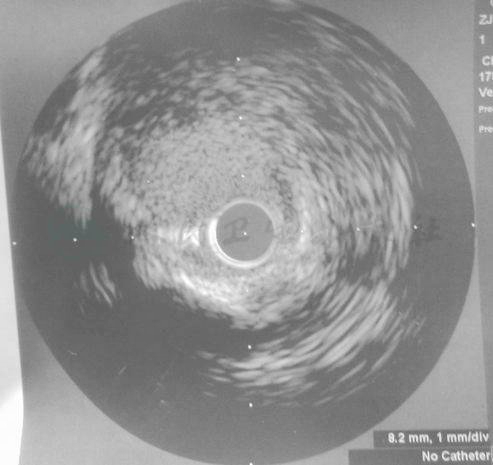

先后前向予Sprinter 1.5mm×15mm球囊、MINI TREK 2.0mm×20mm球囊逐段扩张CTO病变后,造影可见RCA全程显影(图13、图14)。经IVUS检查,可见RCA开口部和近段夹层,以及自开口部至远段全程严重弥漫性病变(图15、图16)。

图15 经IVUS检查,可见RCA开口部和近段夹层,以及自开口部至远段全程严重弥漫性病变

图16 经IVUS检查,可见RCA开口部和近段夹层,以及自开口部至远段全程严重弥漫性病变